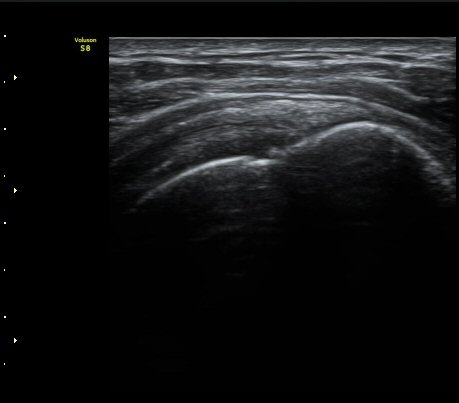

±Ø»ó°Ç Ⱦ´Ü¸é°Ë»ç¿¡¼­ ±Ø»ó°Ç ±ÙÀ§ºÎ¿¡¼­´Â ƯÀÌ ¼Ò°ßÀ» º¸ÀÌÁö ¾ÊÀ¸³ª ±Ø»ó°Ç ¿øÀ§ºÎ¿¡¼­

ÇÇÁú°ñ ¿¬°á ¼Ò½Ç°ú ¹Ì¼¼ÇÑ °ñÆíÀÌ °üÂûµÊ(»çÁø 6, 7).